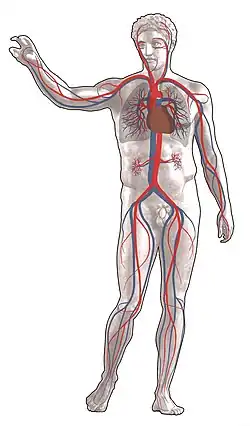

Кровообраще́ние челове́ка — замкнутый сосудистый путь, обеспечивающий непрерывный ток крови, несущий клеткам кислород и питание, уносящий углекислый газ и продукты метаболизма. Состоит из двух последовательно соединённых кругов (петель), начинающихся желудочками сердца и впадающих в предсердия:

- большой круг кровообращения начинается в левом желудочке и оканчивается в правом предсердии;

- ма́лый круг кровообращения начинается в правом желудочке и оканчивается в левом предсердии.

Начинается из левого желудочка, выбрасывающего во время систолы кровь в аорту. От аорты отходят многочисленные артерии, в результате кровоток распределяется согласно сегментарному строению по сосудистым сетям, обеспечивая подачу кислорода и питательных веществ всем органам и тканям. Дальнейшее деление артерий происходит на артериолы и капилляры. Общая площадь поверхности всех капилляров в организме человека примерно 1500 м2[1]. Через тонкие стенки капилляров артериальная кровь отдаёт клеткам тела питательные вещества и кислород, а забирает от них углекислый газ и продукты метаболизма, попадает в венулы, становясь венозной. Венулы собираются в вены. К правому предсердию подходят две полые вены: верхняя и нижняя, которыми заканчивается большой круг кровообращения. Время прохождения крови по большому кругу кровообращения составляет 23—27 секунд.